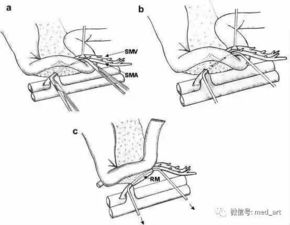

inferior mesenteric artery起源于腹主动脉,沿肠道分布,为肠道提供血液供应,该动脉在解剖学上具有复杂的分支,包括左结肠动脉、乙状结肠动脉等,这些分支进一步为肠道的各个部分提供血液,inferior mesenteric artery的解剖结构在人体内起着至关重要的作用,为肠道的正常功能提供了必要的血液供应。

inferior mesenteric artery在临床上具有重要意义,对于肠道疾病的诊断和治疗,了解inferior mesenteric artery的解剖结构和生理功能至关重要,医生可以通过观察inferior mesenteric artery的血液供应情况,判断肠道疾病的严重程度和预后,在手术中,医生需要了解inferior mesenteric artery的走行和分支情况,以避免在手术过程中损伤该动脉,导致肠道血液供应不足,进而影响肠道功能。